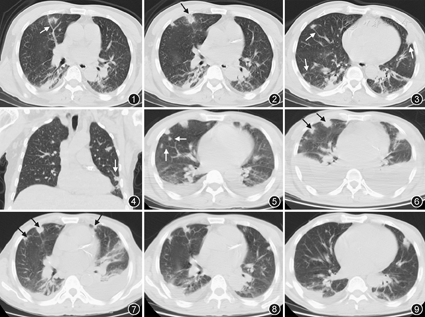

患者男,55岁,因"发热伴咳嗽、咳痰2周"于2014年11月17日入院。患者于2014年11月4日无明显诱因出现发热,体温最高40 ℃,伴畏寒,咳嗽,咳少量黄白色痰。当地医院血培养示金黄色葡萄球菌,对苯唑西林、利奈唑胺、万古霉素均敏感,给予抗感染治疗(具体用药不详),仍持续发热,出现全身多发皮疹及水疱。2014年11月8日就诊于我院,胸部CT(图1,图2,图3,图4)示双肺周边大小不一的多发斑片、结节及条索影,部分结节可见空洞、滋养血管征,行血培养示金黄色葡萄球菌,诊断为"肺炎,金黄色葡萄球菌败血症",给予利奈唑胺静脉滴注6 d,皮肤水疱消退,仍发热。2014年11月15日胸部CT(图5)示双肺斑片、结节影,较前部分增大,部分缩小,双肺下叶部分实变,双侧胸腔积液;腹部CT示脾大,左侧肾盂、肾盏及输尿管积水,给予静脉滴注万古霉素3 d,效果不佳。既往史:2型糖尿病病史10余年,空腹血糖约9 mmol/L,餐后2 h血糖约13 mmol/L;高血压病病史10年;冠心病病史5年;外伤后脑出血病史1年,保守治疗。个人史:吸烟指数60包年;饮酒30余年,白酒200 g/d。体检:体温38.3 ℃,脉率102次/min,呼吸频率26次/min,血压140/79 mmHg(1 mmHg=0.133 kPa),体质虚弱,全身皮肤凹陷性水肿,右前臂皮肤可见直径约2 cm红肿破溃,左前臂可见直径约6 cm皮肤淤斑,臀部散在皮肤破溃结痂。全身浅表淋巴结无肿大。双肺呼吸音粗,可闻及湿啰音。双下肢肌肉萎缩,肌力4级。院外血常规示白细胞为11.53×109/L,血小板为67×109/L;D–二聚体为2 940 mg/L;血生化检测示总蛋白为46 g/L,白蛋白为20 g/L,肝肾功正常;血气分析(吸空气)示pH值为7.56,PaO2为67 mmHg,PaCO2为30 mmHg,SaO2为95%。入院初步诊断:脓毒症,金黄色葡萄球菌肺炎,肾盂积水(左),输尿管积水(左)。

入院后给予万古霉素、头孢哌酮舒巴坦,输注白蛋白、血小板、控制血糖等治疗。血气分析(吸氧2 L/min)pH值为7.52,PaO2为161 mmHg,PaCO2为29 mmHg,SaO2为98%;2次血培养(发热时抽取)为金黄色葡萄球菌,耐药谱同当地医院;1次尿培养示近假丝酵母菌。2次痰培养示鲍氏不动杆菌(++,B级);降钙素原为0.748 μg/L。9项呼吸道病原体抗体、风湿相关检验、尿便常规、心电图等未见异常。心脏超声:肺动脉高压(轻–中度),各瓣膜未见赘生物。复查血常规示白细胞为7.25×109/L,血小板为121×109/L,D–二聚体>1 050 μg/L。血糖控制可,仍间断发热,最高体温在38 ℃左右。2014年11月24日胸部CT(图6)示双肺阴影未见吸收,胸腔积液较前增多。B超见左臂多处软组织脓肿,右上肢、双下肢及臀部炎性包块超声表现。换用替考拉宁、哌拉西林舒巴坦抗感染,并双侧胸腔微创置管,引流液呈淡黄色,胸腔积液培养阴性,胸腔积液常规示漏出液。2014年12月5日胸部CT(图7)可见双肺多发性斑片、结节影部分吸收,胸腔积液减少。并行左臂多处脓肿切开引流,脓液呈暗红色脓血样,培养示金黄色葡萄球菌,每日清洁换药。右股后脓肿行穿刺置管引流。复查消化及泌尿系B超:脾轻大,余未见异常。2014年12月23日胸部CT(图8,图9)双肺多发斑片、结节影大部分吸收,胸腔积液减少。患者体温恢复正常,予拔除胸腔微创置管。予抗生素降阶梯治疗:静脉滴注头孢曲松、盐酸莫西沙星。复查血、尿、痰培养均阴性,其余指标逐渐恢复正常。患者轻微咳嗽,无其他不适,好转出院。最后诊断:脓毒症,脓毒性肺栓塞,多发软组织脓肿。

SPE是肺栓塞的一种少见类型,但病情严重,其特征为含有病原体的栓子脱落后随血流进入肺血管系统导致肺栓塞(或梗死)和局灶性肺脓肿。国内报道的SPE较少,且为个案报道或小样本数的报道[2,3,4]。SPE诊断依靠临床、微生物学及影像学的证据。典型肺CT表现为多发胸膜下外周结节(大小不等,其内空洞多变)、<3 cm的楔形影和滋养血管征[5,6]。其他CT表现有肺实变或浸润影、心包积液、胸腔积液(或脓胸)、纵隔淋巴结肿大等。本例患者胸部CT表现为肺周边多发大小不等结节影、楔形影,其内部分可见滋养血管征及空洞,以及胸腔积液,少量心包积液。此外SPE应与血栓性肺栓塞、血源性肺部感染、转移性肿瘤、韦格纳肉芽肿等病鉴别。